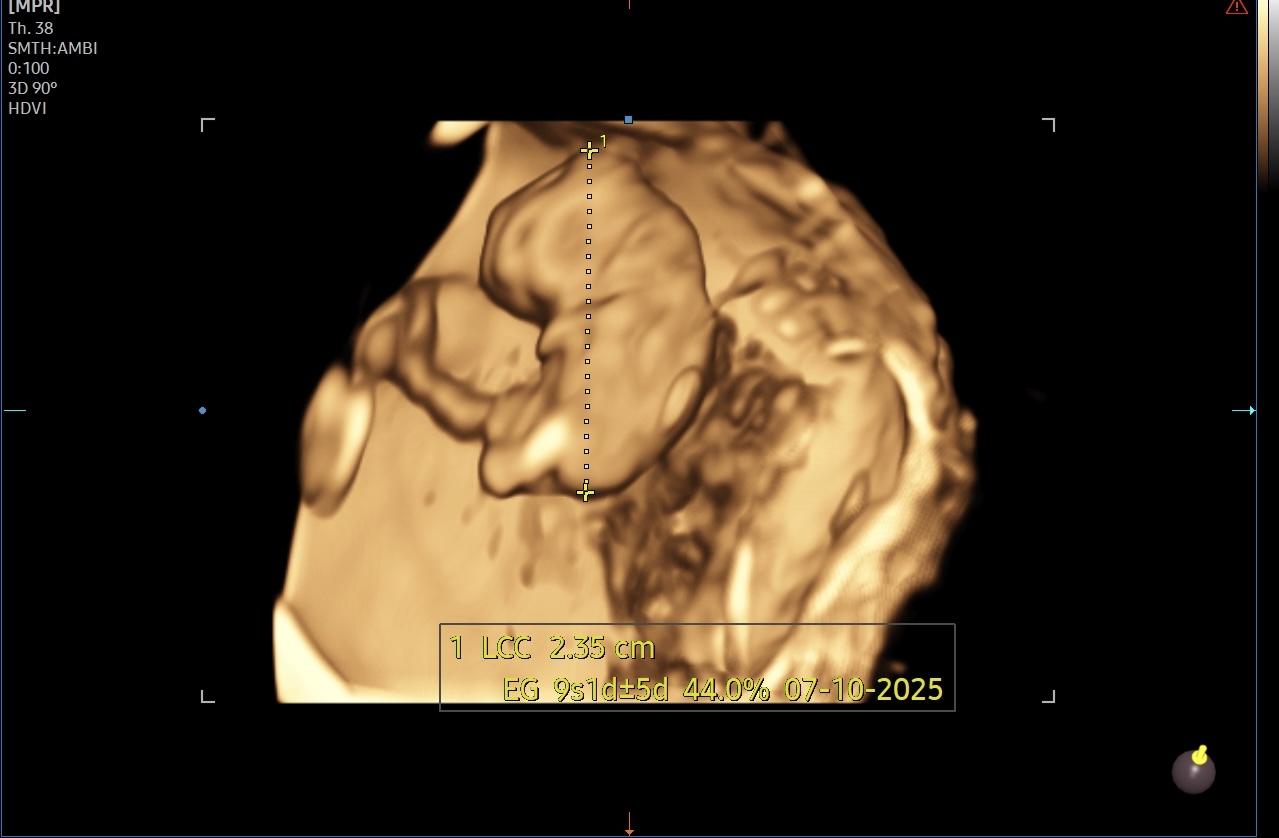

1-ый триместр беременностиСходила на второе узи. Не знаю почему врач назначил так рано повторное, думаю что ходила больше из-за анализов. Она проверила базовые анализы типо группу крови, воспаления, инфекции. Попросили сдать анализ на Цитомегаловирус, слышала про краснуху, ветрянку, токсоплазу, но почему именно этот, не знаю. Может в этом районе это самое опасное. 🤷🏼♀️ По узи все хорошо, сердечко бьется сильно. Никаких гематом и отслоений. Отправили домой до первого скрининга. Муж словил паническую атаку во время узи, только когда вышла заметила. Сказал, что перед узи разнервничался, вдруг не будет сердечка. Боже, милый 🥹 Говорю ем: «Видишь, ноги твои, длиннющие какие» 😃